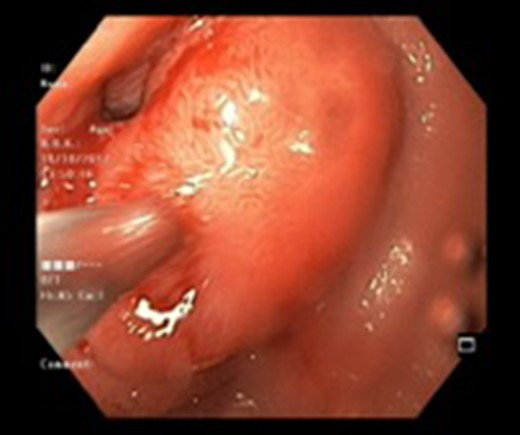

There were three males and one female who had Brunner’s gland hyperplasia as the pathological finding in their surgical specimens following operations for duodenal lesions. Their mean age at presentation was 39.7 ± 10.14 (range: 30–52) years and their presenting features were abdominal pain in two patients, vomiting (2), and upper gastrointestinal bleeding (2). The duration of their symptoms varied between 4 days and 4 years prior to presentation. All patients underwent an upper gastrointestinal endoscopy (Figs 1 and 2) and abdominal computed tomography(Figs 3 and 4) scans as part of their evaluation. The details of patient presentation, evaluation, surgical procedure and outcomes are described in Table 1.

| Case 2 | 44/M | 4 days | Malena, fatigue requiring blood transfusions | 60 × 45 mm2 mildly enhancing solid mass involving second and third part of duodenum with exophytic contour bulge likely polypoid lesion (Fig. 4) | A Large friable polypoidal lesion at junction of second and third part of duodenum | Non-specific chronic duodenitis with focal mild dysplasia | Transduodenal polyp excision (Fig. 5) | 2 | 1 | 5 |

Two patients underwent a pancreaticoduodenectomy, one underwent distal gastrectomy with Billroth II gastrojejunostomy, and one patient underwent transduodenal polyp excision (Fig. 5). Their mean ICU stay was 1.25 ± 0.95 (range: 0–4) days and postoperative hospital stay was 6.5 days (range: 5–8 days). Two patients had Grade I and two patients had Grade II complications. One patient required blood transfusion and other required prolonged nasogastric tube retention in view of persistent vomiting. There was no mortality. All patients are on regular follow up and after a median duration of 11 months they are all symptom free.

Intra-operative photograph showing the polypoid lesion in the second part of duodenum after a duodenotomy.